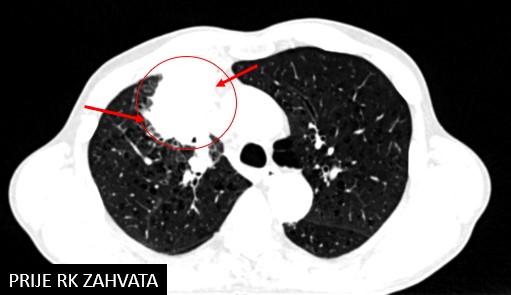

Bolesnik, rođen 1954.

Ca planocellulare bronchi lobi superioris pulmonis lateris dextri cum lymphadenopathia mediastinalis (PD-L1 2%) (2019.)

C

hemotherapia cum gemcitabin/cisplatina (4 cy, 5.7. - 12.9.2019.)

SBRT tm prim. et meta mediastini (12./2019.)

SABR meta pulmonis (12.12.2022.)

Immunotherapia cum nivolumab

Rezultat – 36 mjeseci nakon RK

smanjenje tumora pluća za 85.9 %